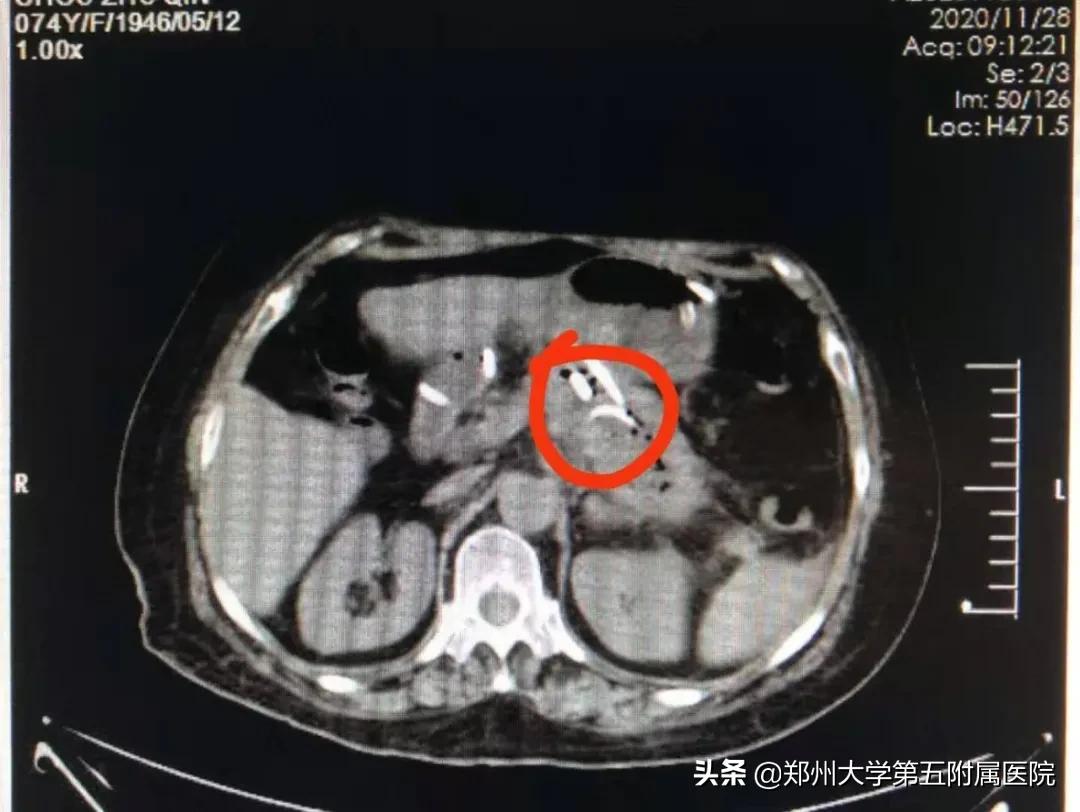

术后给予积极的抗感染治疗,在刘谦副主任医师和王文真医师以及护理团队的精心治疗下,术后患者腹胀明显减轻,3天后复查彩超及CT囊肿基本消失。由于创伤小,又是在无痛麻醉状态下施行操作,整个过程患者没有任何痛苦,术后第二天便下床活动。

▲ 术后复查CT